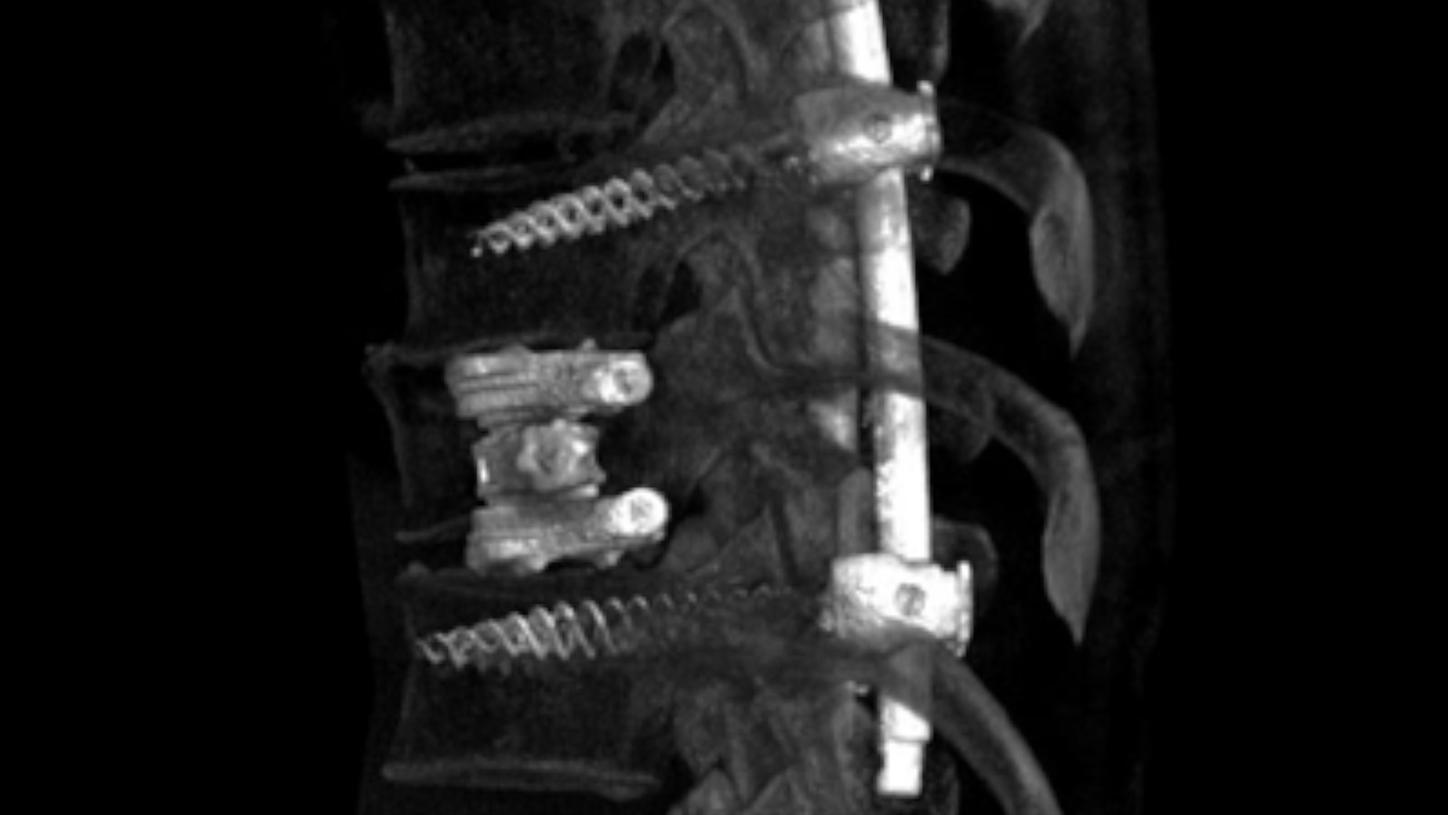

Spinal disorder: Imaging of the spine used for spinal disorder diagnosis

Spinal disorder

In spinal surgeries, minimally invasive implantations cannot be monitored based on eyesight alone, so high-quality interoperative imaging is crucial for precise outcomes with lower risk factors. Our imaging solutions provide 2D and 3D visualization to support you during image-guided spine surgery procedures. Combining intraoperative imaging with optical navigation can greatly boost surgical precision and help you reduce the radiation required for guidance even further.